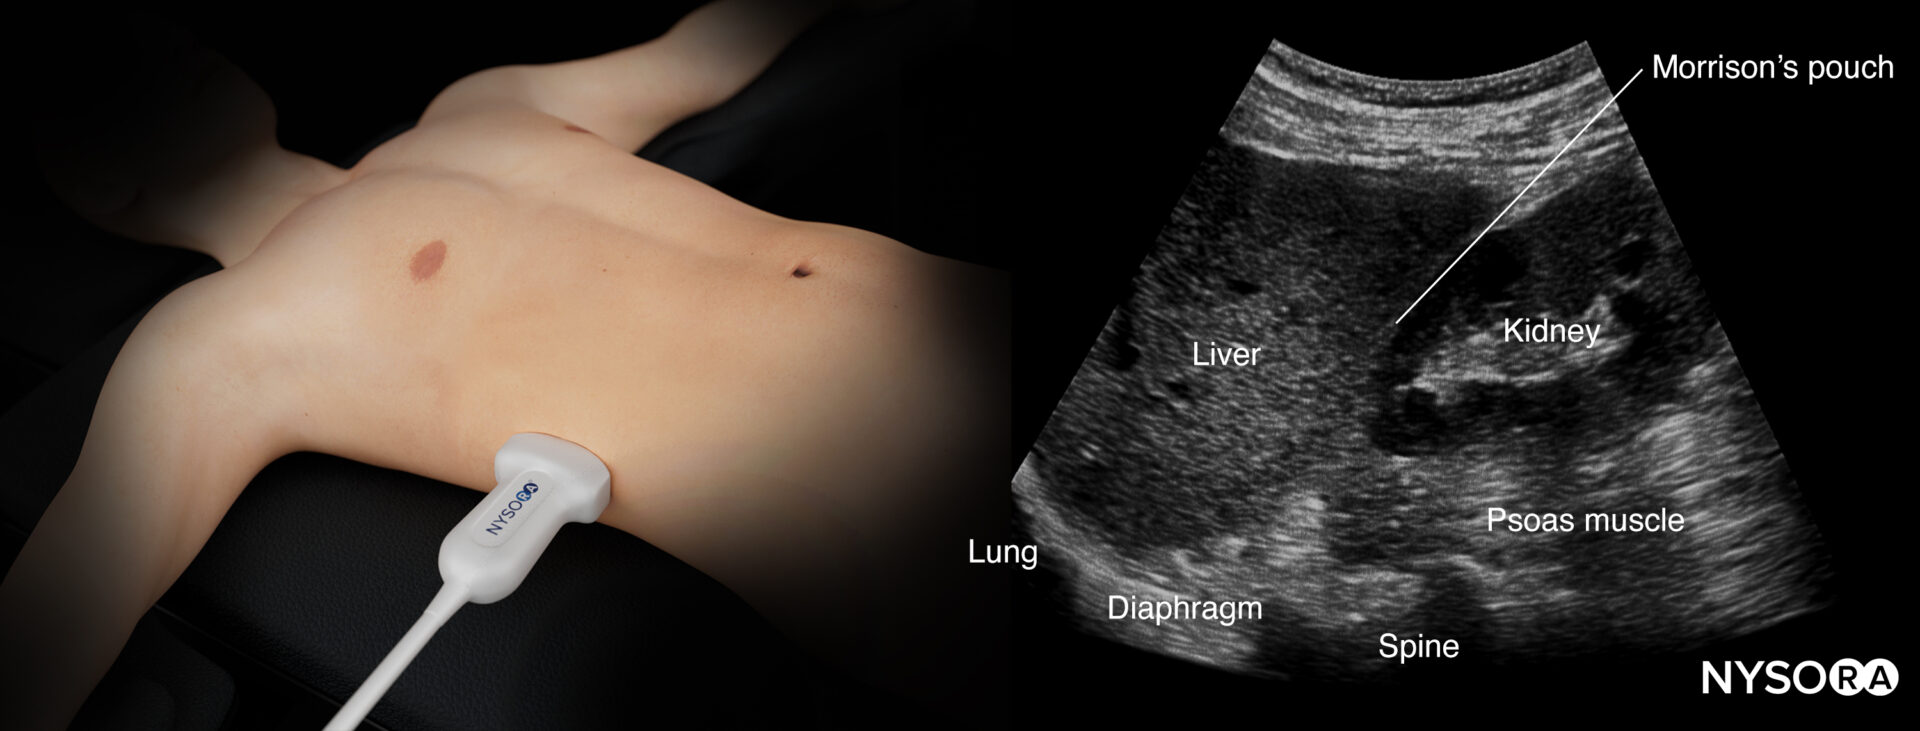

Right upper quadrant (RUQ)

Detects free fluid in the right thorax and abdomen.

- Position the transducer between the mid- and posterior axillary lines at the level of the xiphoid process, with the orientation marker facing the patient’s head.

- Scan caudally until you visualize the liver and the kidney; fluid usually collects between the liver and the kidney, i.e., Morrison’s pouch.

- Structures of interest: lung, diaphragm, liver, kidney, Morrison’s pouch (virtual space between liver and kidney)

Ultrasound anatomy of the right upper quadrant and relevant anatomical structures.

Reverse ultrasound anatomy of the right upper quadrant and relevant anatomical structures.

Free right intraperitoneal fluid collects between the liver and the kidney (Morrison’s pouch). If intrathoracic free fluid is present, it can be identified above the diaphragm.

Free intraperitoneal fluid is often found between the liver and the kidney, i.e., Morrison’s pouch.